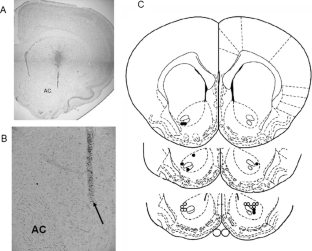

Fig. 1